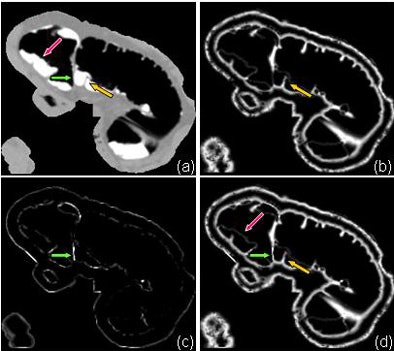

| Example of the structural responses obtained by the analysis of the submerged soft-tissue structures and the local isosurface roughness analysis. (a) Original VC image. (b) The structural response from the Hessian matrix. A submerged fold (orange arrows) is enhanced. (c) The local isosurface roughness. A tagging-tissue-air layer (green arrow) is enhanced. (d) The integration of (b) and (c). Both the submerged fold (orange arrow) and the tagging-tissue-air layer (green arrow) are enhanced, whereas the lumen-tagging layer (red arrow) is suppressed. The integrated structural responses are used in the level set method for preserving the submerged soft-tissue structures while removing the tagged materials. |